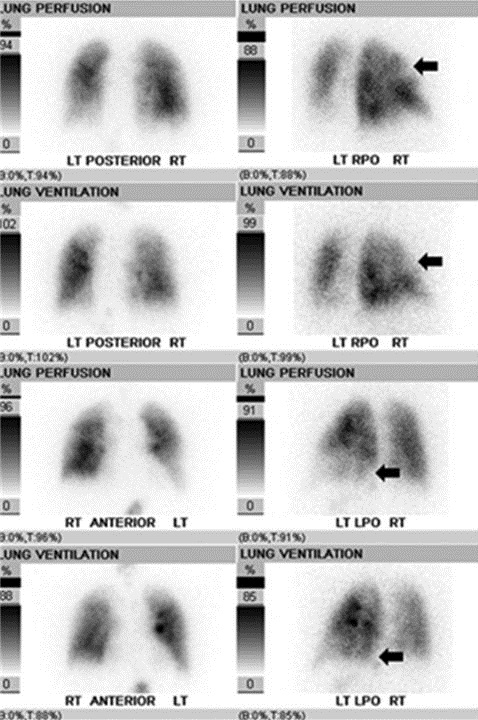

Southwest Journal Of Pulmonary Critical Care Imaging The